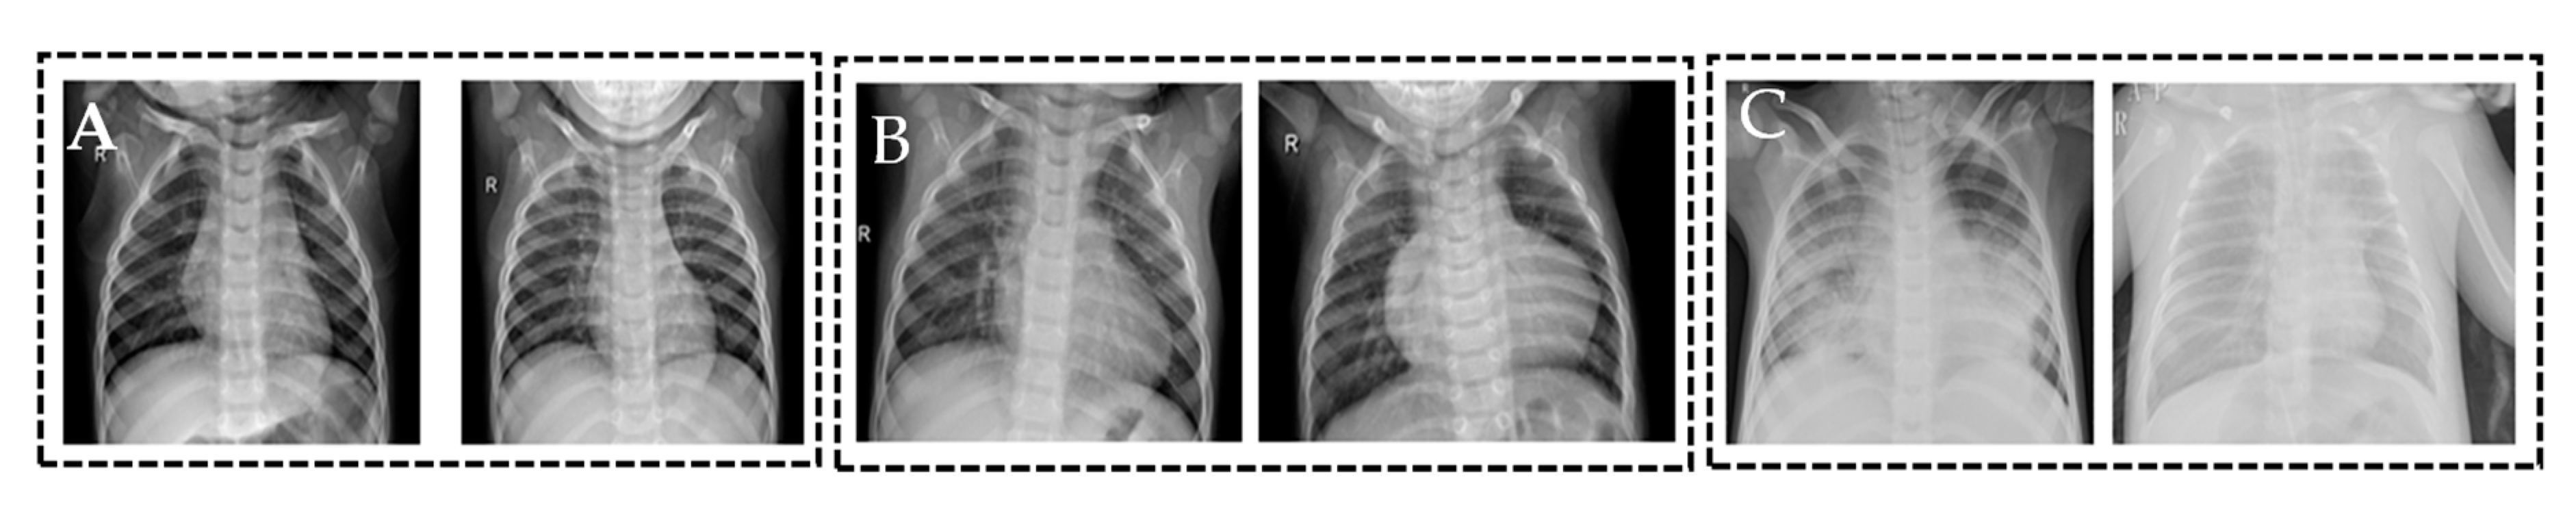

Table 2 shows a number of train (using augmentation) and test images for different evaluation experiments. Four different algorithms were trained using the training dataset and then evaluated on test dataset. Figure 7 shows two samples for normal, bacterial, and viral pneumonia chest X-ray images.

Figure 7.

Data samples from the dataset, (A) shows normal cases, (B) shows bacterial pneumonia cases, and (C) shows viral pneumonia cases.